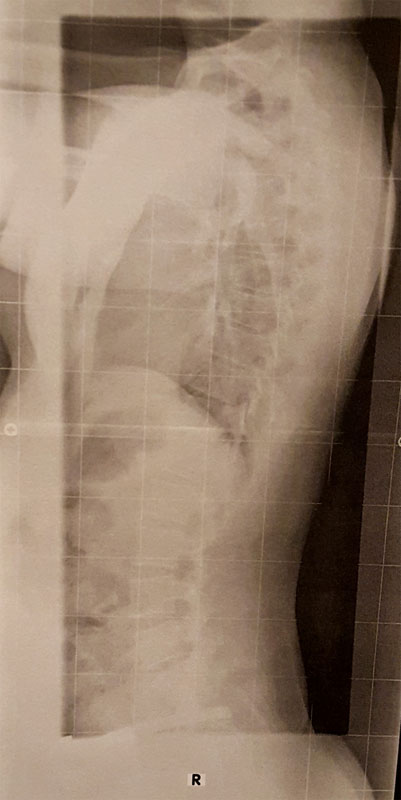

Ihm viel direkt auf den ersten Blick auf was bei mir das Problem ist und konnte dies anhand eines Röntgenbildes auch bestätigen.

- Streckfehlhlatung in der LWS, sprich die Lordose ist so gut wie aufgehoben, im oberen Bereich der BWS ist die kyphose zu flach, und in der HWS ebenfalls überstreckt, Neigt sogar leicht zur Kyphose.

- In der BWS liegt eine minimalste Skoliose von 2.2 grad vor die keinerlei Krankheitswert hat. So gleicht mein Körper anscheinend den minimalen Beinlängenunterschied aus. Dieser ist auch nicht der Rede wert.

- Der 5. Lendenwirbel ist mit dem Steißbein verschmolzen, dies ist aber wohl seit meiner Geburt der Fall und aufgrund des sauberen "zusammenwuchses" sollte dies auch nicht weiter tragisch sein. DR. Hoffmann ist darauf auch gar nicht eingegangen.

- ich stehe im Lot und habe keinerlei verknöcherungen, oder sonstiges was mich an einer Korrektur hindert, sprich es ist rein muskulär bedingt

- Ansonsten ist nichts auffälliges zu entdecken, sowie keinerlei Verschleiß zu erkennen.

Für weitere Meinungen hänge ich noch die Röntgenbilder mit an.